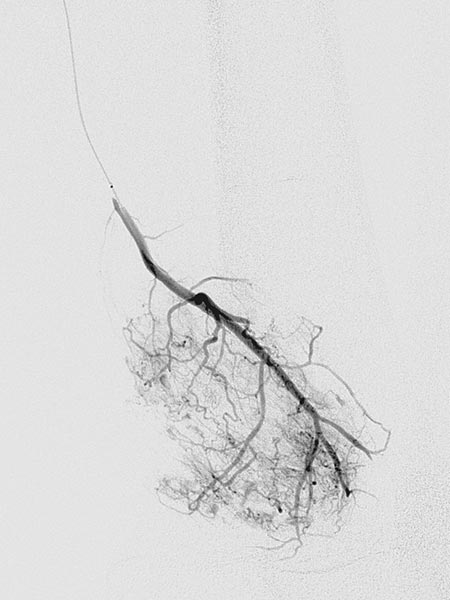

Die digitale Subtraktionsangiographie (DSA) in der früharteriellen Phase zeigt eine, aufgrund der chronischen Mehrdurchblutung erweiterte, zuführende Arterie (sogenannte Feederarterie), in diesem Fall eine Arteria genu superior medialis.

Die digitale Subtraktionsangiographie (DSA) in der arteriellen Phase 2 s später zeigt einige kleinere arteriovenöse Fisteln.

Die digitale Subtraktionsangiographie (DSA) in der arteriellen Phase zeigt im Gegensatz zu einer arteriovenösen Malformation nochmals 4 s später keinen direkten frühvenösen Abstrom des Kontrastmittels, sondern eher ein Pooling-Phänomen.

Superselektive Sondierung der Arterie mit einem Mikrokatheter zeigt wiederum die multiplen, feinen arteriovenösen Fisteln, jedoch nicht den für eine AVM typischen sofortigen venösen Abstrom. Diese starken arteriovenösen Fisteln in die VM sind ungewöhnlich ausgeprägt.